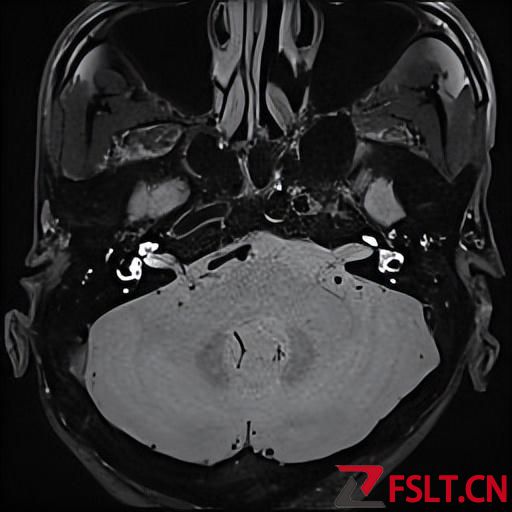

由于被這個病折磨的太久了,患者和家屬決定還是做手術(shù)徹底治療比較好。耳鼻喉梅曉峰主任和鄭立崗主任帶領(lǐng)手術(shù)團隊認真分析患者的各項術(shù)前檢查后一致認為患者梅尼埃病診斷明確,有反復(fù)發(fā)作,而且多次住院及長期藥物治療效果不佳,聽力下降也非常嚴重,有內(nèi)淋巴囊減壓手術(shù)的適應(yīng)癥。

手術(shù)由梅曉峰主任和鄭立崗主任主刀,這次做的是全麻內(nèi)淋巴囊減壓手術(shù),在耳后做切口后暴露乳突骨皮質(zhì),打開乳突腔,暴露后半規(guī)管和內(nèi)淋巴囊,切開內(nèi)淋巴囊放置引流裝置??p合切口并放置負壓引流。整個的手術(shù)用時約2個小時,非常順利。術(shù)后第二天查房患者無明顯的不適,無手術(shù)相關(guān)的并發(fā)癥。自覺耳鳴消失,聽力較術(shù)前稍有提高,無眩暈發(fā)作。